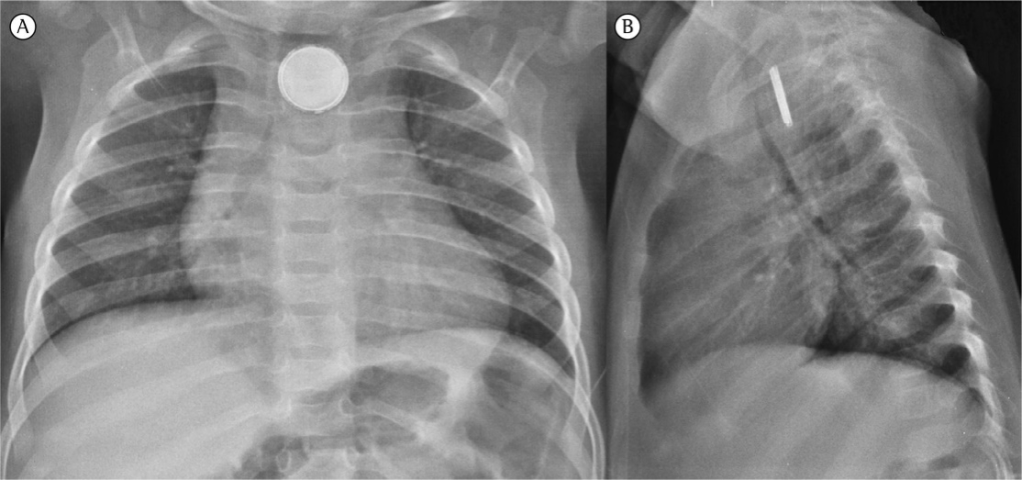

On physical exam, vitals are notable for temperature of 99.7oF, heart rate 110 bpm, blood pressure 100/60 mmHg, respiratory rate 22/minute, and oxygen saturation of 95% on room air. Capillary refill time is 3.5 seconds. The patient is awake and alert but is tired appearing and pale. You observe the patient cough intermittently throughout the exam, but otherwise is sitting upright in mom’s lap without apparent distress. Lung exam demonstrates equal breath sounds and no wheezing or audible stridor. Examination of the nares and throat does not show any blood. There is no pain elicited from abdominal palpation. Though his symptoms appear consistent with an upper respiratory infection, the hemoptysis warrants a chest x-ray, which is shown below.

Initial management is supportive care, with special attention to patients who are exhibiting signs of shock, hematemesis, or airway obstruction and require resuscitation. All patients should be kept NPO until battery is localized. In stable patients, an X-ray should be obtained immediately to determine the location of the button battery. X-ray will show a “halo,” or “double ring” sign in the AP view and a “step off” sign in the lateral view. This is created by the anode can sitting atop the larger cathode can and can be helpful in distinguishing a button battery from a coin, or other flat, radiopaque foreign body. The most likely point where a button battery will get stuck is at the level of the cricoid cartilage, followed by at the level of the carina and aortic arch and remainder getting stuck at the lower-esophageal junction.

Radiology reads the AP and Lateral chest X-ray as a button battery lodged in the patient’s esophagus. The ED team calls poison control, who refers them to the Button Battery Ingestion Algorithm. The patient is made NPO and further history is obtained. The father remembers earlier that morning he had noticed the patient playing with a musical greeting card, which now no longer makes music. He checked the card and found that the button battery inside the card was missing.